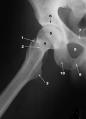

Fractura de caderaEl ranelato de estroncio reduce en un 36 por ciento el riesgo de sufrir fracturas de cadera en postmenopáusicas con osteoporosis, según concluye el estudio Tropos, sobre el tratamiento de la osteoporosis periférica, que se publica en el último número del Journal of Clinical Endocrinology and Metabolism.

El Tropos es un ensayo en fase III de tres años de duración que ha comparado el ranelato de estroncio con placebo en 5.091 mujeres de más de 70 años y baja densidad ósea en el cuello femoral. Uno de los autores españoles del estudio, Adolfo Díez, jefe del Servicio de Medicina Interna del Hospital del Mar, en Barcelona, ha explicado cómo la nueva molécula supone una nueva herramienta terapéutica "para combatir el deterioro físico que produce una enfermedad tan compleja como es la osteoporosis".

Este ensayo clínico ha demostrado que dosis diarias de 2 gramos al día de ranelato de estroncio, un agente fisiológico que reequilibra el metabolismo óseo a favor de la formación de hueso nuevo, disminuyen no sólo el riesgo de sufrir fracturas de cadera, sino también el de padecer todo tipo de fracturas periféricas. Además, ha confirmado también su eficacia frente a las fracturas vertebrales.